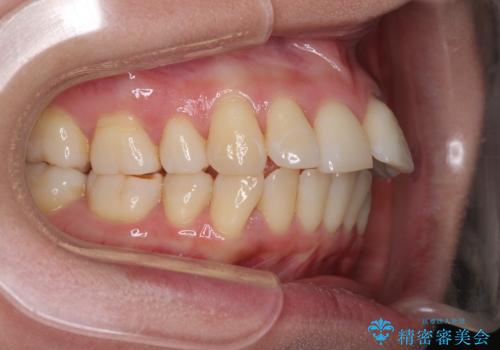

後戻りで突出した口元を引っ込めたい インビザライン矯正治療

- 上の前歯の出っ歯を治したいとのことで来院された患者様です。

後戻りによる再矯正というもともあり、インビザラインを希望されていました。

上顎の歯は後方移動とIPR(歯と歯の間を削る)によって口元が引っ込むように、下顎は歯列全体の拡大とIPRによって上顎とバランスよく咬み合うように設計し、インビザラインにより治療を行うこととしました。

治療を開始して暫くして、勤務先から2年以上帰国することができず、それまでの移動がほとんど後戻りしてしまい、帰国後に再度後戻りをリカバリーするための治療を行うこととなりました。

5年以上の治療期間がかかりましたが、気になっている部分を改善することができました。